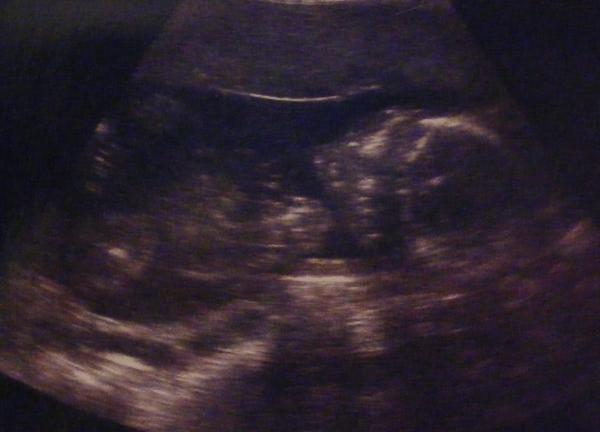

Heut beim FA war es echt toll, er hat lange geschallt, Krümelchen war auch endlich mal wach und hat gewunken. Haben sogar gesehen wie der Mund auf und zu ging.

Es ist jetzt schon etwa 14cm von Kopf bis Steiß groß, liegt in Beckenendlage und der Doc meint das es zu 70% ein Mädel wird! :D *freu*

Mal schauen ob sich seine Vermutung dort bestätigt. Wie sagte er heut... Also icke seh da keinen Pimmel!

Das Bildchen ist leider nicht ganz so toll aber ich zeig es euch trotzdem, ist sozusagen die Rückenansicht.